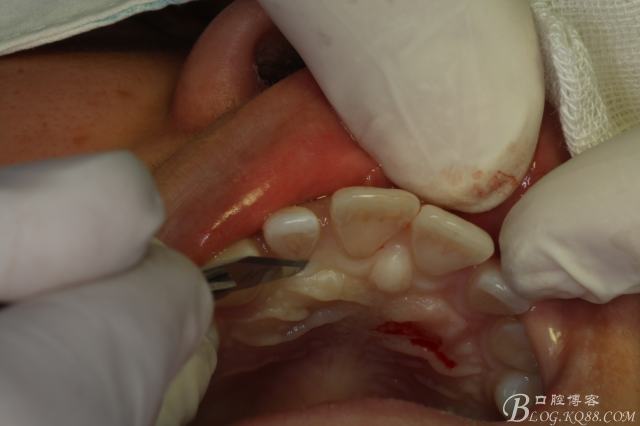

圖6.行腭側(cè)齦溝內(nèi)水平切口。

圖7.翻瓣